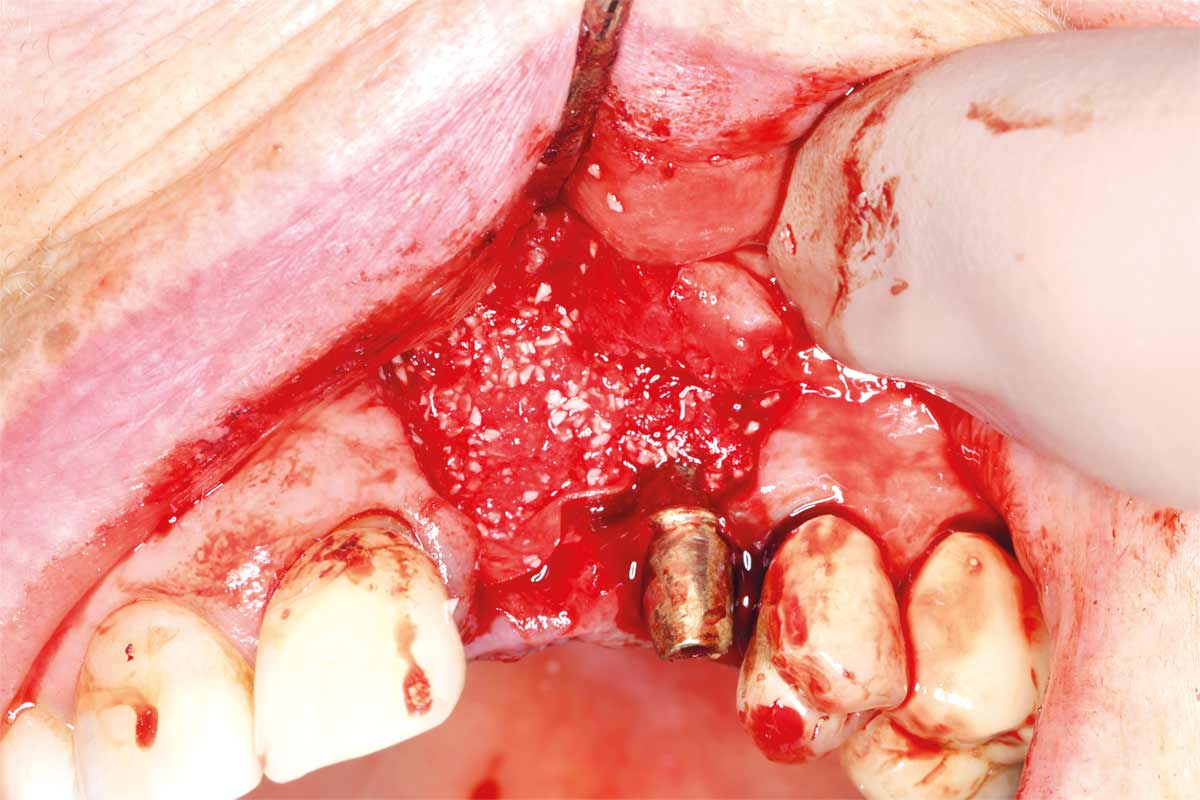

Ridge management following implant explantation - Dr. P.-Y. Gegout & Prof. Dr. O. Huck

Pre-operative: loss of interdental papilla between 12 and 11 associated with gingival inflammation and pus